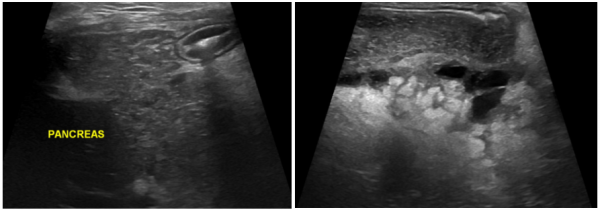

초음파 검사에서는

-췌장 종대

-실질의 불균질 변화

-주변 복막 지방 염증

-복수 소견이 확인되었습니다.

이러한 변화는 중증 강아지 급성췌장염에서 흔히 관찰됩니다.